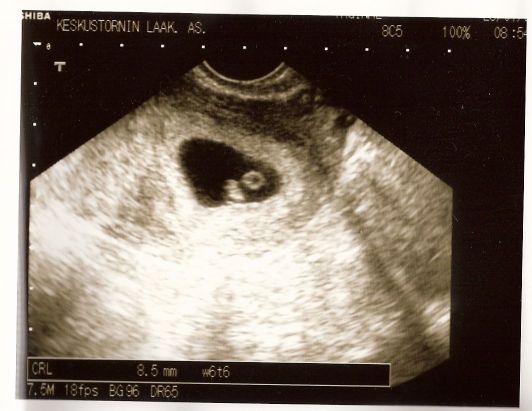

Nämä kaksi kuvaa ovat ihan ensimmäiset, varhaisultrassa otetut kuvat:

Varhaisultra1

-20.10.2007 (RV 5+4) Eilen tilasin ajan varhaisultraan. Aika saatiin maanantaille 29.10, jolloin on kulunut 6+6 viikkoa, jolloin jotain katkarapua muistuttavaa pitäisi olla jo näkyvissä. Vähintäänkin pitäisi selvitä, että tyyppi on oikeassa paikassa. Uutena oireena on ilmennyt hajuaisti muutoksia, esim. astianpesukone tuoksahti ihan kuvottavalle.

-30.10.2007 (RV 7+0) Eilen käytiin varhaisultrassa yksityisellä Tapiolan keskustornissa tarkistamassa että onko siellä joku hengissä ja että se joku on oikeassa paikassa. Lääkärinä oli Seija Kaukoranta, joka sai heti kättelyssä näkyville ruskuaispussin ja sikiön, jossa voitiin nähdä sykkivä sydän. Mukaan saatiin kuvat, äitiyskortti ja lausunto jossa kerrotaan, että kohdussa on 1 sikiöpussi, pituus 8,5 milliä, vastaa 6+6 raskausviikkoa. Hyvä sydämensyke.